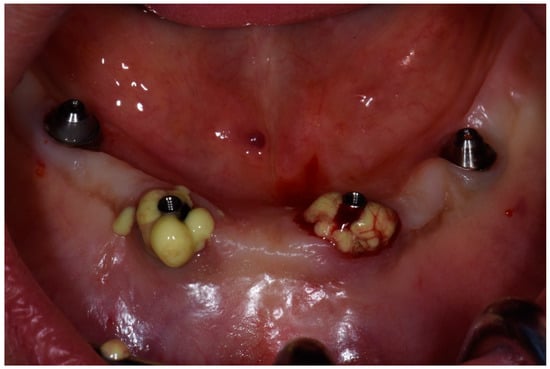

After removing the prosthetic rehabilitations, diagnosis of the soft tissue was done. Peri-implant assessment (PPD, TL, BI, PI, and mobility) and, subsequently, assessment of color, contour, consistency of soft tissues was performed. Individual oral hygiene instructions including re-education and motivation if needed was done. Bidimensional radiographic assessment (with periapical and panoramic radiograph) was performed (Figure 10 and Figure 11).

Figure 10.

X-ray of 3.5 dental implant in patient before treatment.

Figure 11.

X-ray of 4.5 dental implant in patient before treatment.

The clinical assessment allowed finding a probing depth of 6 mm mesial/circumferentially to 3.5 with bleeding in the two lower jaw distal implants and a probing depth of 4–2.5 mm mesial/circumferentially with bleeding in the two lower jaw central implants. In the upper jaw, a probing depth of 1–2 mm was found. None of the implants showed mobility.

A bidimensional radiographic assessment of the lower jaw and upper jaw implants (with periapical and panoramic radiograph) was done. In the lower jaw implants, a concave bone resorption can be observed of about 4 mm mesial and distal to both distal implants (3.5 and 4.5). No bone resorption was revealed on the two lower jaw central implants and on the four implants positioned in the upper jaw.